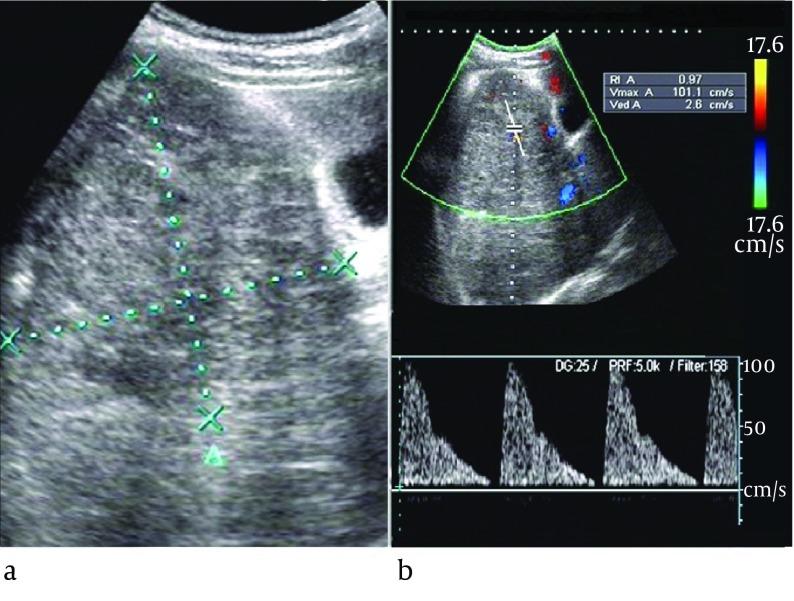

Compared with HBL group, the age of IHH group was much younger (5.8 months vs. 35.1 months, P = 0.000), the AFP elevation was less likely to be detected in IHH group (23.1% vs. 89.5%, P = 0.000). Although the color flow were the same commonly observed (61.5% vs. 52.6%, P > 0.05), the spectral Doppler showed IHH was less likely to appear as arterial flow with resistance index (RI) > 0.7(12.5% vs. 75.0%, P < 0.05), characterized by arterial flow with RI < 0.7 and/or venous flow. Combined the clinical features including age (< 6 months) and normal AFP level yielded high capability in differential diagnosis, with sensitivity, specificity and Youden index of 77% (10/13), 95% (36/38), and 0.72, respectively. When combined clinical features (age and AFP) and spectral Doppler as the diagnostic criterion for distinguishing these cases with positive color flow signals, the sensitivity, specificity, accuracy and Youden Index were 88%, 95%, 89% and 0.83, respectively.

The clinical features are effective indicators for distinguishing IHH from HBL, and the spectral Doppler may be a useful adjunct parameter for differential diagnosis.